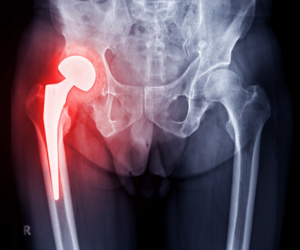

Comprehensive Joint Replacement Surgery

Expertise in total hip replacement, partial knee replacement, and complex revision surgeries means you’re in capable hands for every stage of your joint care journey.